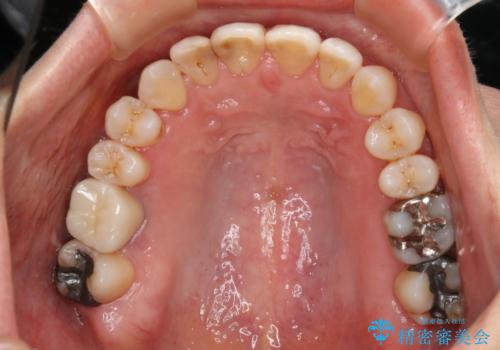

- 右上の小臼歯が二本とも90度捻じれてしまっており、奥歯の噛み合わせに問題が生じていました。

歯を抜いてワイヤー治療を行うという選択肢もありましたが、

奥歯の被せ物の形を適切にすることで非抜歯でも治療が可能であると判断し、

非抜歯、インビザラインでによるマウスピース矯正治療を行うことにいたしました。

今回は右上の奥歯に入っていた銀歯の形が悪く、そのせいで歯を並べるスペースが足りない状態でした。

右上の歯の被せ物を作りなおし、適切な歯の大きさに代えてあげることによってスペースを作りました。

また、それだけではスペースが足りない為右上の奥歯は遠心移動を行っています。